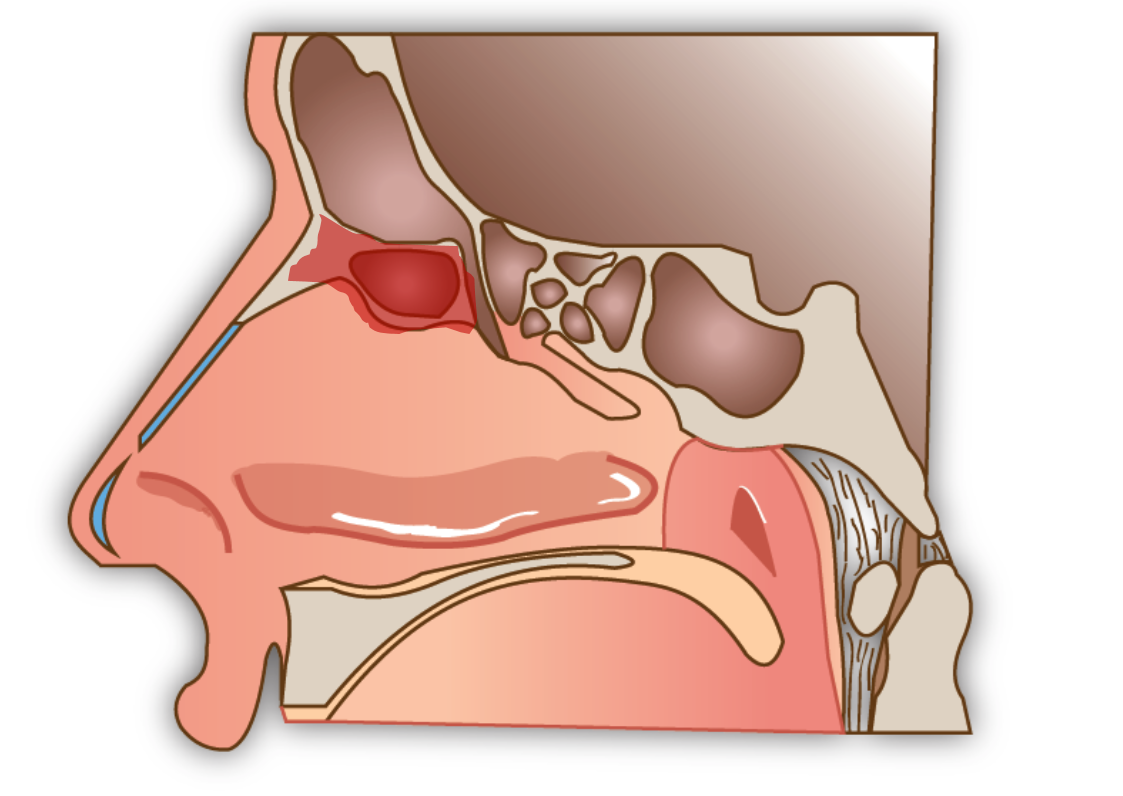

L’ouverture simple du sinus frontal (Sinusotomie Draf I)

Elle consiste en l’ouverture endoscopique, par les narines, des cellules de l’ethmoïde antérieure qui se situent en dessous du sinus frontal pour avoir accès à celui ci.

La sinusotomie frontale Draf II

Elle utilise la même technique endoscopique mais l’ouverture du sinus frontale est élargie dans sa partie basse à l’aide de fraises pour permettre un meilleur drainage